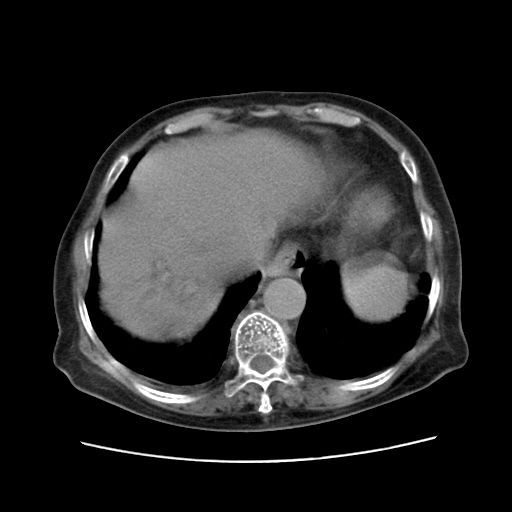

女,77.无不适

肝脏变异、异位胆囊,肝右叶肝内胆管结石并肝内胆管扩张。

肝内胆管扩张,胆囊炎,胆囊窝积液。 右侧胸腔少量积液。

肝脏变异

胆囊未见明显显影

肝右叶肝内胆管结石并肝内胆管扩张。另:慢性胆囊炎!胆囊窝积液!